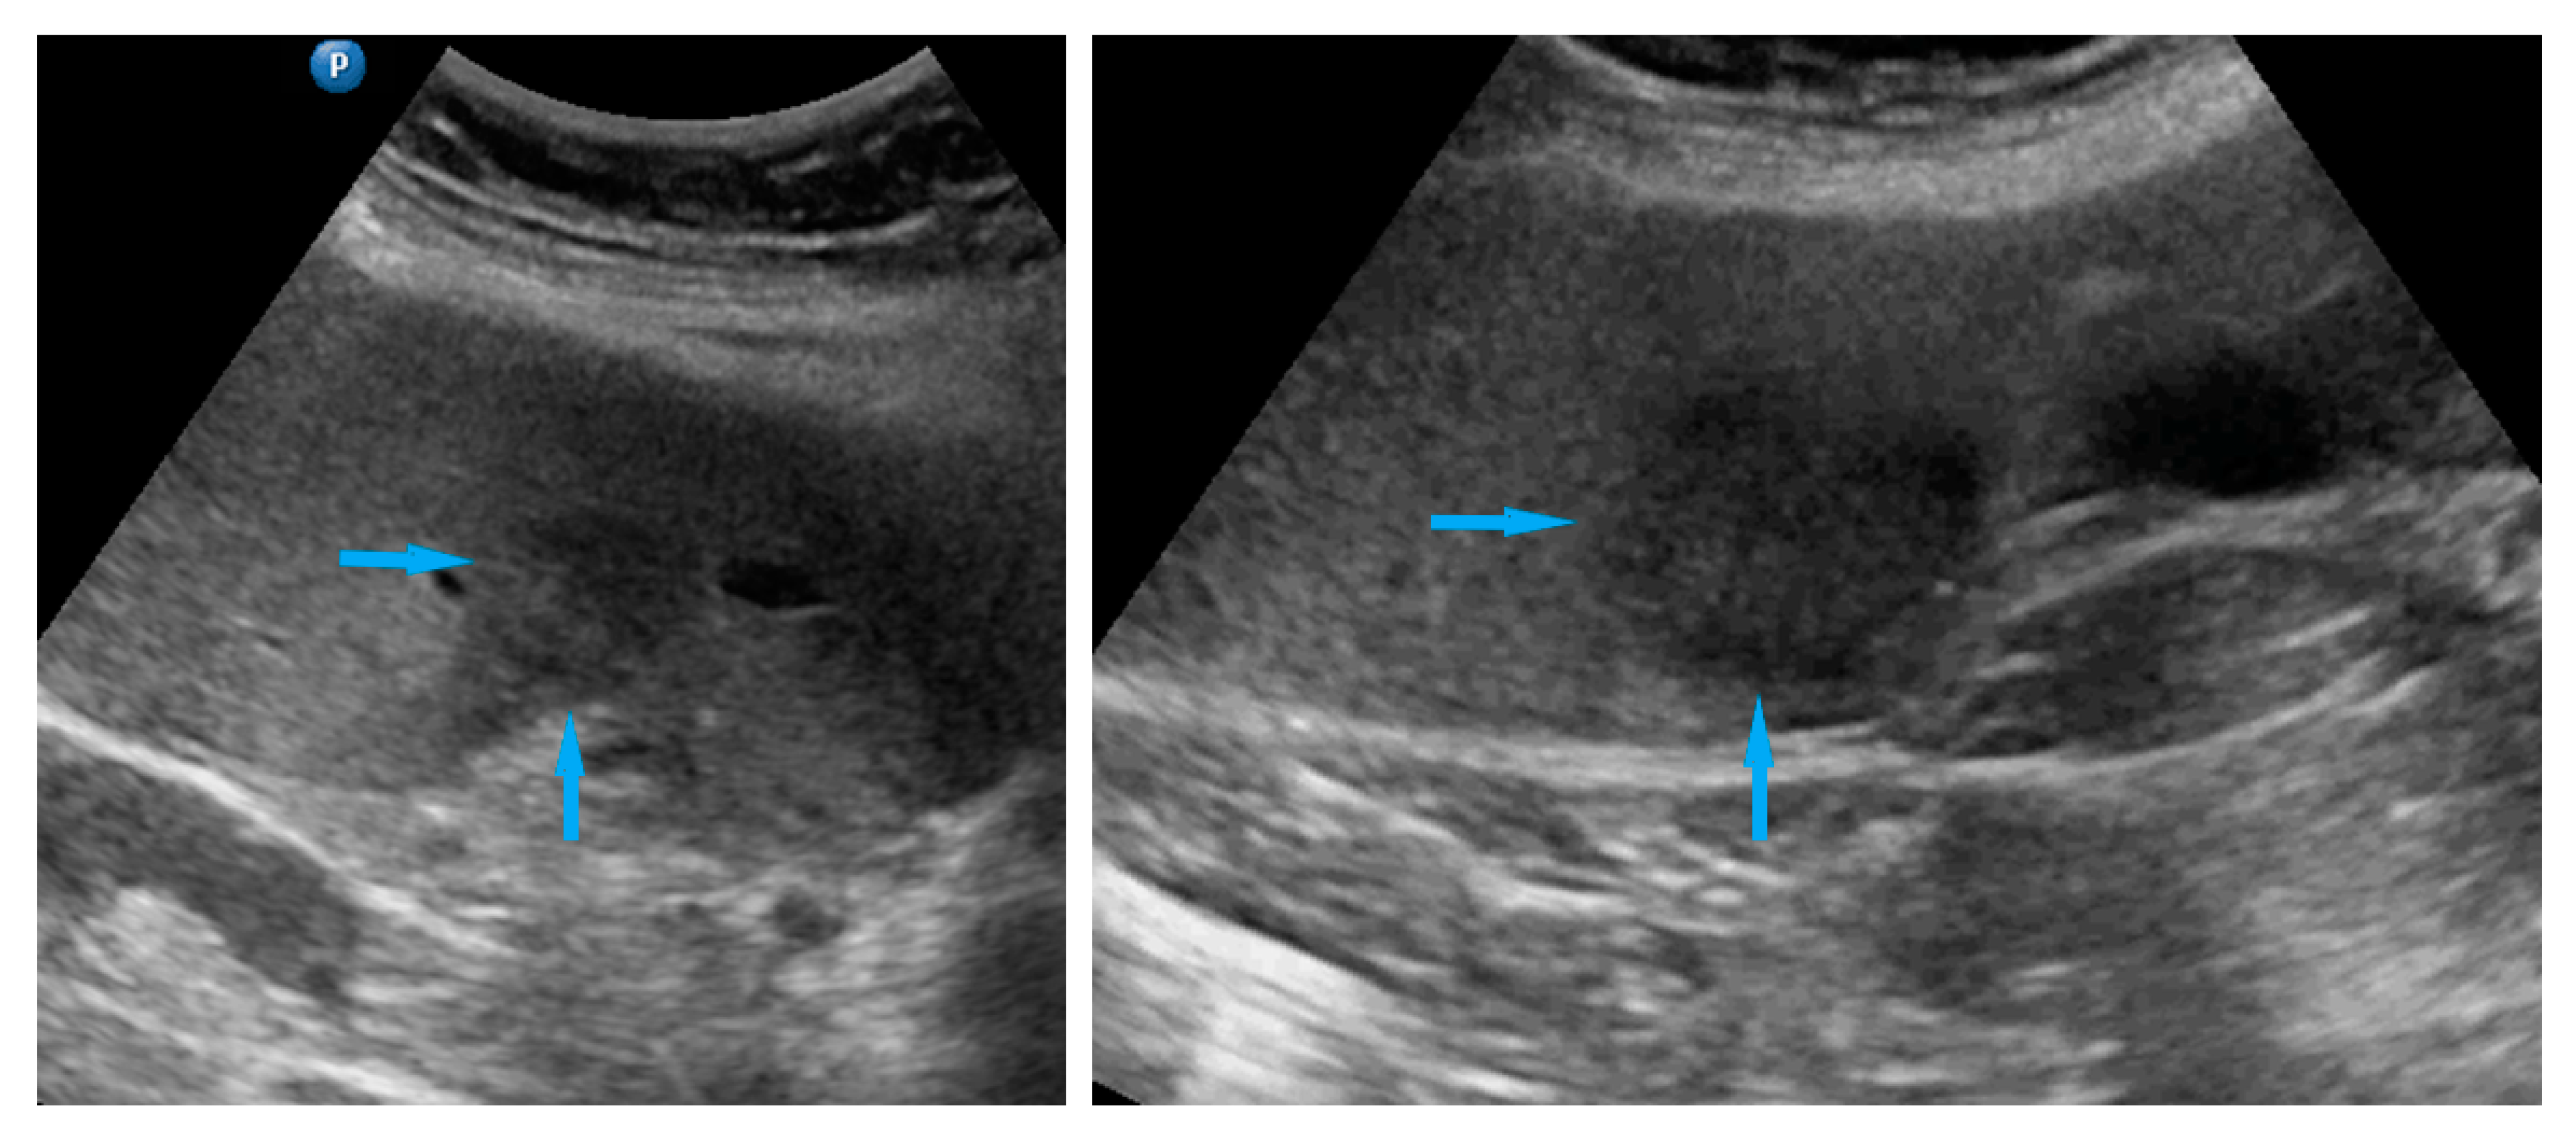

| Diaphragm, right | Carcinomatosis manifests as hypoechogenic lesions over the peritoneal surface of the right diaphragm. | Figure 10 | Video S10 |

| Diaphragm, left | Carcinomatosis manifests as hypoechogenic lesions over the peritoneal surface of the left diaphragm. | Figure 11 | Video S11 |